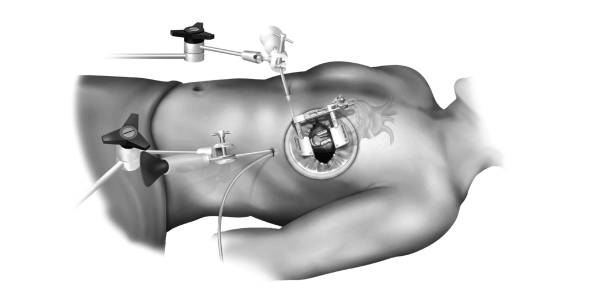

All You Need To Know About Minimally Invasive Cardiac, Minimally Invasive Cardiac Surgery (MICS)-CABG - Yashoda,

Minimally Invasive Cardiac Surgery (MICS)-CABG - Yashoda, Dr M M YUSUF || One among the few minimally invasive and,

Dr M M YUSUF || One among the few minimally invasive and, fcvm-09-1053572-g001.jpg,